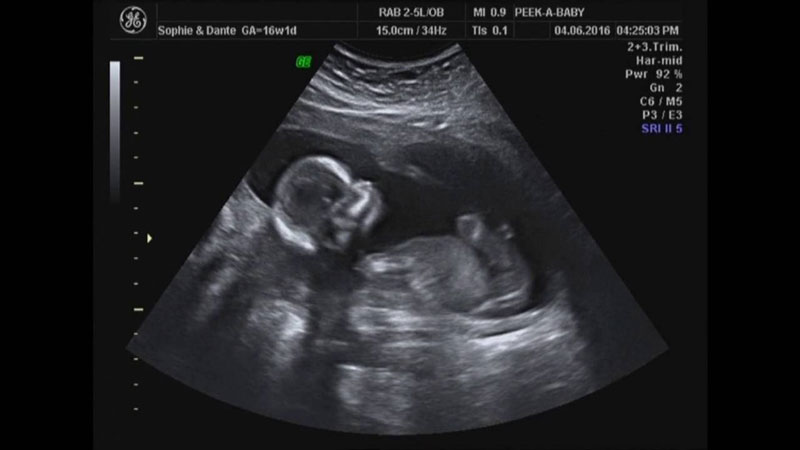

Siêu âm thai nhi là biện pháp kiểm tra thăm khám định kỳ, qua đó giúp theo dõi và phát hiện kịp thời những dấu hiệu bất thường trong sự phát triển của thai nhi. Trong thai kỳ sẽ có những mốc thời gian siêu âm quan trọng mẹ bầu không được quên, bao gồm mốc 18 tuần. Siêu âm mốc 18 tuần để làm gì? Chúng ta sẽ cùng nhau tìm hiểu qua bài viết sau đây.

Siêu âm thai nhi là kỹ thuật sử dụng đầu dò của máy quét siêu âm để ghi lại hình ảnh thai nhi đang phát triển trong bụng mẹ. Bên cạnh đó, thông qua hình ảnh siêu âm thai 18 tuần còn giúp các bác sĩ phát hiện bất kỳ dấu hiệu bất thường nào trong thai kỳ. Do đó, phụ nữ mang thai cần thăm khám theo lịch khám thai bác sĩ đưa ra, điều này giúp cho hành trình mang thai luôn được bảo vệ an toàn.

Siêu âm thai nhi là một phần không thể thiếu trong quá trình thăm khám thai định kỳ. Phương pháp không xâm lấn này không gây đau đớn và an toàn cho cả mẹ và bé. Bằng cách di chuyển đầu dò siêu âm trên bụng người mẹ, các bác sĩ có thể ghi lại hình ảnh của thai nhi trong bụng mẹ, giúp bà mẹ tương lai có thể nắm bắt được sự tăng trưởng, chuyển động lẫn sự phát triển tổng thể của bé yêu.

Siêu âm mốc 18 tuần để làm gì ngoài việc sàng lọc, dự đoán nguy cơ bệnh lý? 18 tuần cũng còn là thời điểm để bạn tận mắt chứng kiến sự lớn lên của con mình. Thông qua những hình ảnh của bé yêu được phương pháp siêu âm ghi lại, các ông bố bà mẹ tương lai có thể chứng kiến và yên tâm hơn với sự phát triển của thai nhi khi có các chỉ số về cân nặng, kích thước phù hợp với tuổi thai.

Ở giai đoạn này, em bé đã phát triển các cơ quan và bộ phận cơ thể. Siêu âm thai nhi trong tuần 18 - 22 là điều quan trọng nhất để phát hiện sớm các bất thường về cấu trúc và hình thái. Các bác sĩ quan sát tỉ mỉ não, hộp sọ, mặt, cột sống, thành bụng, tim, dạ dày, thận, mạch máu và tứ chi. Việc kiểm tra kỹ lưỡng này cho phép xác định các vấn đề tiềm ẩn như sứt môi, xương lệch và khe hở cột sống,…